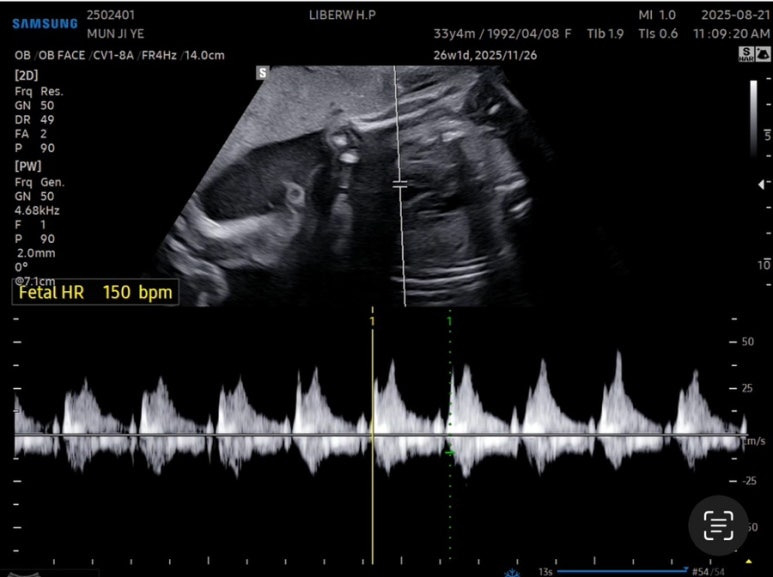

심장박동수 150bpm